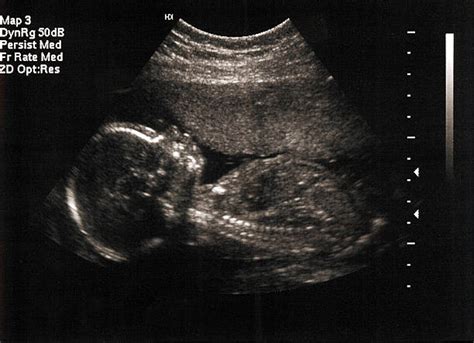

Bábätká sa v maternici začínajú pohybovať už od siedmeho alebo ôsmeho týždňa - dlho predtým, než to matka ucíti. Od deviateho týždňa začínajú hýbať rukami a nohami a od jedenásteho týždňa začínajú hýbať hlavičkou zo strany na stranu. Dieťa sa potom môže pretiahnuť a zívať. Do akej miery je dieťa aktívne, ste pravdepodobne videli na ultrazvuku v dvanástom týždni. Okolo 20. až 24. týždňa tehotenstva sa aktivita dieťaťa zvyšuje. Začne kopať, otáčať sa a dokonca čkať.

Placenta je životne dôležitý orgán, ktorý sa vyvíja počas tehotenstva a poskytuje rastúcemu plodu potrebné živiny a kyslík a zároveň odvádza odpadové produkty. Jednou z rôznych polôh, ktoré môže placenta zaujať, je predná poloha, čo znamená, že sa nachádza na prednej stene maternice. Predná placenta označuje placentu, ktorá je implantovaná na prednej (čelnej) stene maternice. Túto polohu možno identifikovať počas bežných ultrazvukových vyšetrení, ktoré sa zvyčajne vykonávajú v prvom alebo druhom trimestri tehotenstva.

Placenta, ktorá je prichytená k stene maternice a poskytuje dieťaťu počas tehotenstva živiny, môže byť v pozícii, ktorá bráni cíteniu prvých pohybov. Placenta sa obvykle prichytáva k zadnej strane maternice v blízkosti chrbtice. Keď sa ale placenta nachádza na prednej strane maternice, môže jej umiestnenie tlmiť pohyby bábätka až do neskorého štádia tehotenstva. Placenta, ktorá sa na začiatku alebo uprostred tehotenstva nachádza v dolnej časti maternice v blízkosti krčka maternice, sa väčšinou presunie v neskoršom štádiu tehotenstva vyššie a nespôsobuje žiadne problémy. Ak však placenta v blízkosti krčka maternice alebo nad ním zostane aj v neskorom štádiu tehotenstva, môže počas pôrodu spôsobiť problémy. Keď placenta maternicové hrdlo zakrýva, hovorí sa jej vcestné lôžko (placenta previa) - také umiestnenie je pomerne vzácne. Umiestnenie placenty sa v priebehu tehotenstva sleduje, aby bolo možné akýkoľvek problém riešiť s predstihom.

Prvorodička cíti prvé pohyby bábätka približne v 20. týždni, druhorodička už v 18. týždni. Druhorodička má viac skúseností, nezmýli si pohyby dieťaťa napríklad s pocitom nafúknutia. Brušná stena druhorodičky je citlivejšia. Záleží aj na prirodzenej vnímavosti, ako veľmi je žena schopná vcítiť sa do svojho tela a rozlišovať jeho impulzy. Uloženie placenty: ak je placenta na prednej strane maternice, výrazne tlmí pohyby smerom k bruchu ženy.